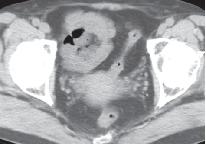

最后,做了腹盆增强CT。典型的图像如下:

上面4图分别为:平扫、动脉期、门脉期、延迟期

影像表现:于升结肠前方可见一不规则团块状脂肪密度影,周围脂肪密度增高,升结肠周围可见饱满淋巴结,邻近肠壁有轻微增厚,无明显脓肿及肠梗阻征象。

诊断:升结肠肠脂垂炎。